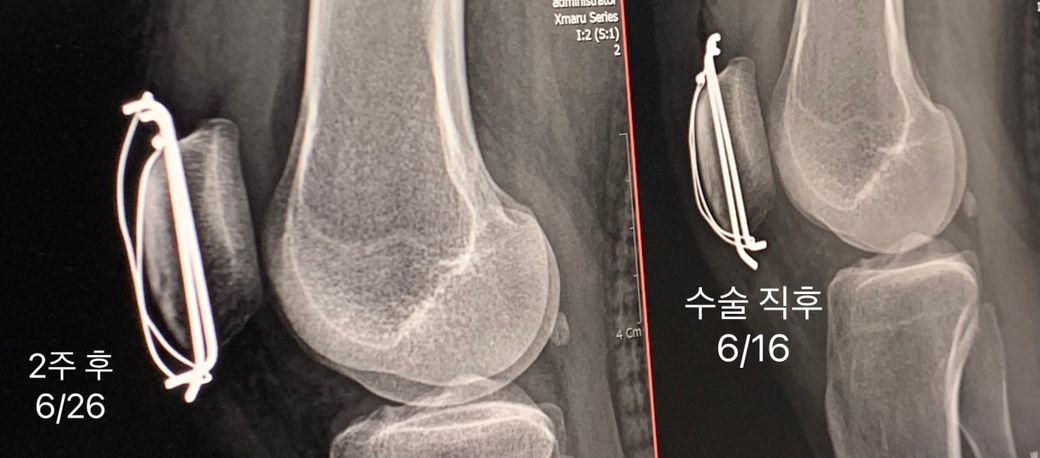

슬개골 골절 후 철심수술 와이어변형 이대로 두어도 괜찮을까요?

6/13일 슬개골 골절로 철심 박는 수술 후 붕대 및 지지대 처리를 하고 입원하였습니다 6/27일 퇴원 예정이라 6/26일 엑스레이를 찍었는데 와이어가 돌아가서 갑자기 통깁스를 하게 되었어요 의사분 말로는 와이어가 돌아가도 재수술이나 향후 재활엔 크게 문제가 없으나 고정이 필요하다고 해 일주일간 통깁스를 하게 된건데 정말 문제가 없는게 맞나요?

• 2번 째 사진

13일날 슬개골 골절 수술을 하셨고 금속 와이어 핀 삽입 수술을 하신 상태이고 26일 검사 결과 와이어가 돌아간 것을 확인하고 재수술 없이 고정만 하면 되므로 통깁스 처방을 해주신 상태라면 와이어 돌아감이란 와이어가 약간 돌아가거나 위치가 어긋나도 큰 문제가 없을 수 있습니다.

뼈가 붙는데 필요한 압박력이 약해지면 고정력이 저하되고 연부조직에 자극을 줄 수 있으며 고정력이 부족하면 깁스로 추가 안정성을 확보해야 합니다.

재 수술을 권하지 않은 이유로는 뼈 유합이 잘 되고 있으며 와이어의 위치가 내부에서 살짝 회전한 정도라면 재수술이 필요하지 않을 수도 있습니다.